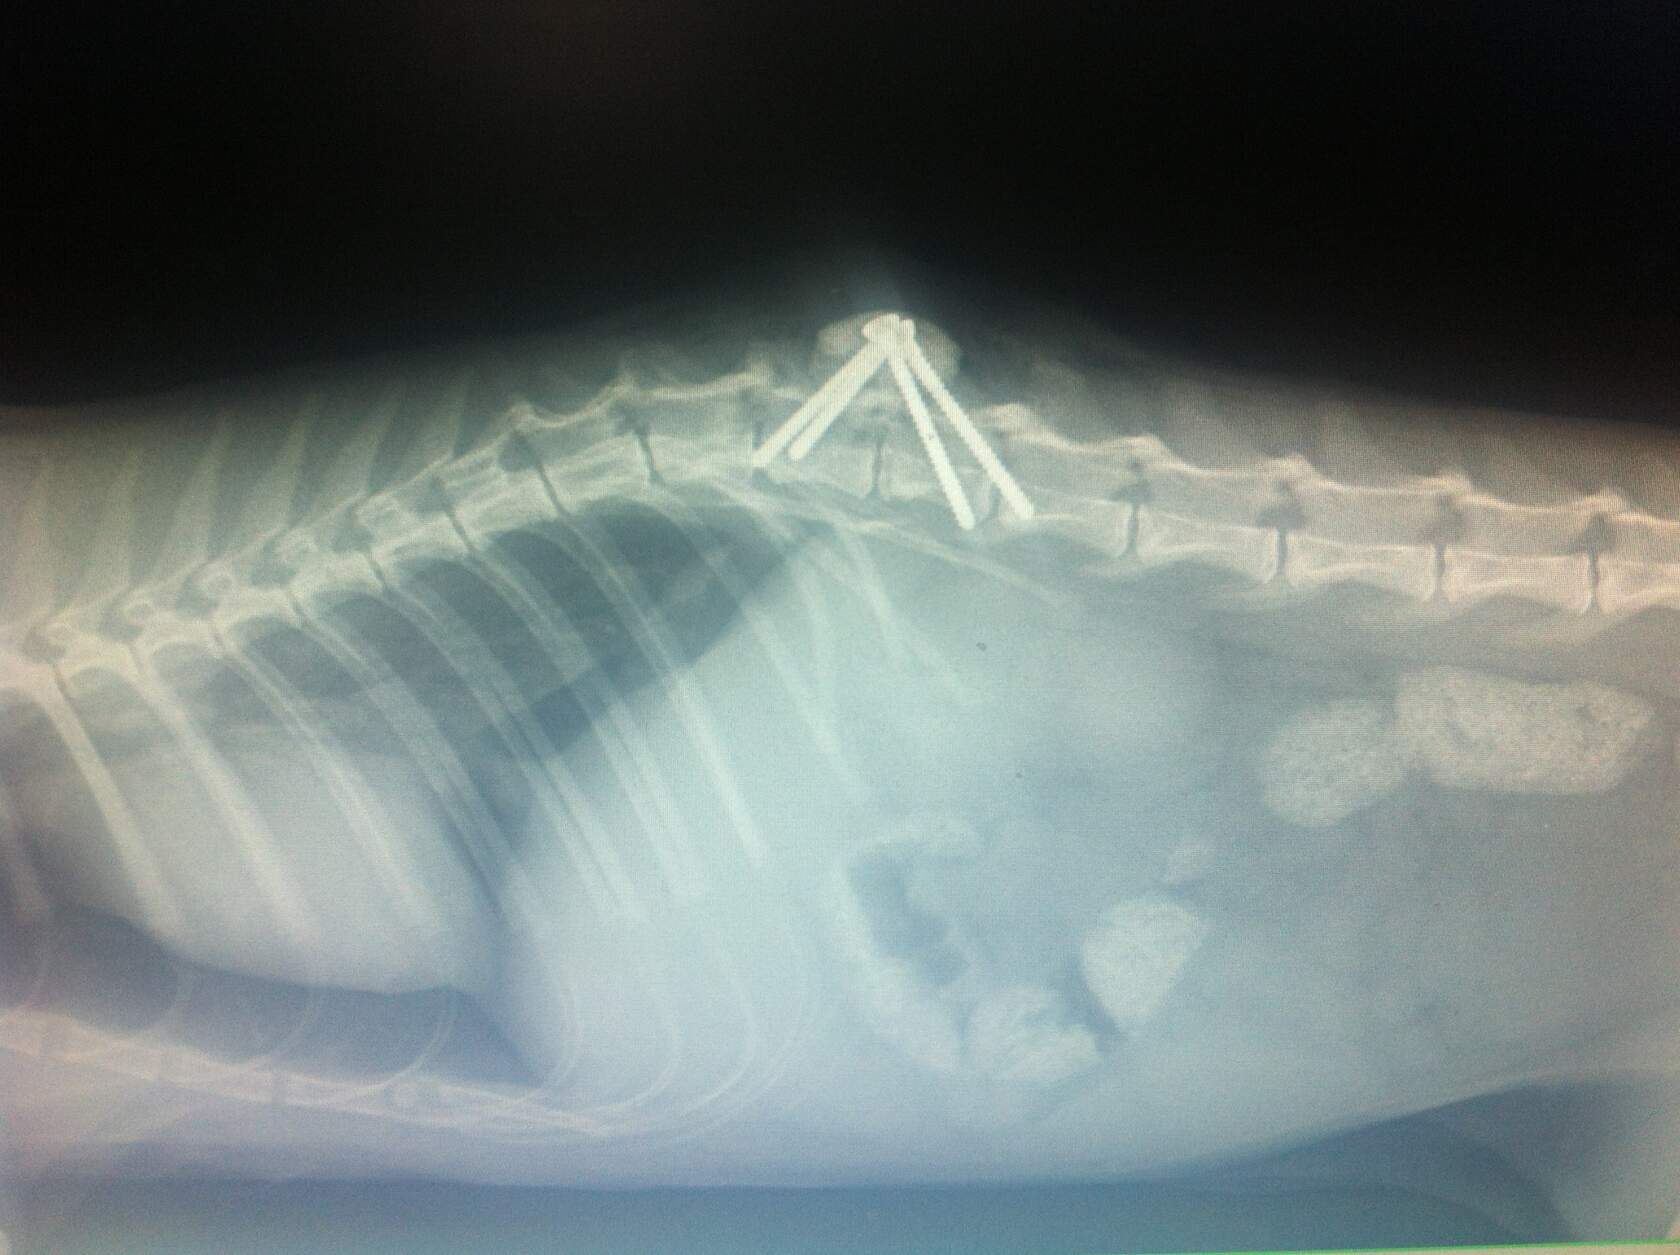

Дорогие друзья! Сегодня я забрала Валдая из стационара клиники Сотникова и перевезла в стационар Альтервета. Операция сделана с блеском. Котик чувствввует себя очень хорошо. Почти сразу после операции съел две банки паштета. Клиника Сотникова дала нам космические скидки без всяких просьб с моей стороны. По прейскуранту только операция стоит тридцать тысяч, а нам всё обошлось в двадцать. Не сдаёмся и вместе с котиком учимся жить и быть счастливыми в любом состоянии.

Дорогие друзья! Сегодня я забрала Валдая из стационара клиники Сотникова и перевезла в стационар Альтервета. Операция сделана с блеском. Котик чувствввует себя очень хорошо. Почти